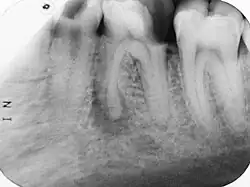

Im Verlauf einer odontogenen Infektion stirbt unbehandelt die Pulpa ab und die Keime breiten sich im System der Wurzelkanäle aus. Der Körper reagiert mit einer Entzündung des Zahnhalteapparates (Parodontitis apicalis) im Sinne einer Abwehrreaktion. Eine Parodontitis apicalis kann in einer akuten oder einer chronischen Form vorliegen. Die akute Form ist oft mit Schmerzen verbunden, sie kann unter Umständen röntgenologisch nur schwer verifiziert werden, während eine chronische Parodontitis apicalis bei einer Auflösung der Knochenstruktur im Bereich der Wurzelspitze im Röntgenbild als Aufhellung sichtbar sein kann. Im Röntgenbild erscheint die Aufhellung dunkel, da das Röntgenbild ein Negativ darstellt.

Nach einer Lokalanästhesie erfolgt die Längenbestimmung des Wurzelkanals oder der -kanäle (anhand eines Röntgeneinzelbilds in Verbindung mit speziellen Messnadeln oder auf elektrischem Weg durch Endometrie). Anschließend werden die Kanäle mit Handfeilen oder maschinell angetriebenen rotierenden Instrumenten konisch erweitert („aufbereitet“). Durch Spülungen mit verschiedenen Lösungen, wie z. B. NaOCl, 3-prozentige H2O2-Lösung, EDTA oder CHX, werden Verunreinigungen aus den Kanälen entfernt, die Schmierschicht beseitigt und Mikroorganismen bekämpft. Mittels Laser kann vor der Abfüllung der Kanäle zusätzlich zu den üblich verwendeten Spüllösungen eine Desinfektion erfolgen. Die Spüllösungen können durch Ultraschall aktiviert werden, um die Wirkung zu verstärken. Auf diese Weise können auch Kanalverzweigungen und infizierte Dentinbereiche desinfiziert werden, die einer instrumentellen Aufbereitung nicht zugänglich sind. Auf Endodontie spezialisierte Zahnärzte verwenden bei der Wurzelkanalbehandlung ein Operationsmikroskop, das mit seiner zusätzlichen Lichtquelle mit koaxialem Licht und der Vergrößerung das Auffinden und Betrachten der Kanaleingänge erleichtert.

Der Ablauf einer Wurzelkanalbehandlung am Zahn 17

-

Röntgenaufnahme vor Wurzelkanalbehandlung -

Zahn eröffnet, Pulpa soll entfernt werden -

Pulpa exstirpiert -

Messaufnahme -

Drei Kanäle aufbereitet und ausgeformt -

Oft haben obere Molaren allerdings vier Kanäle -

Alle vier Kanäle abgefüllt -

Kontrollaufnahme nach Wurzelkanalbehandlung -

Deckfüllung -

Kontrollaufnahme nach 20 Monaten